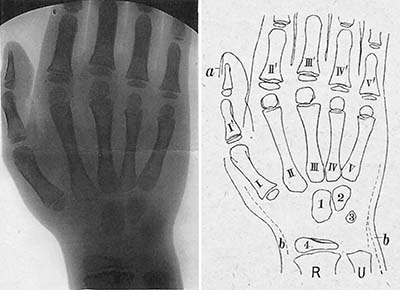

《1918-20-正常四肢骨のレントゲン写真図譜》

藤浪剛一(朝香屋書店,1918-20)

藤浪は序文で,欧米のようなレントゲン図譜が本邦にはないことを憂い,かねてよりこれを企画していたものの,出版者が写真を鮮明に印刷する技術を持たず実現できなかったが,本書の出版社である朝香屋の主人がこれを引き受けてくれてようやく発刊できたと述べている.レントゲン図譜と銘打っているが,その内容は専ら四肢骨の正常像で,小児の骨化中心の出現に主眼が置かれている.藤浪は,ウィーン留学中に手根骨の骨化順序に関する論文を2篇著しており,その延長上にあるものと思われる.

第一輯から第四輯まで四分冊で,それぞれ手関節,肘・肩関節,足関節,膝関節の正常像を扱い,全58葉のレントゲン写真とそのスケッチが,小児から成人まで年齢順に供覧されている(図10,図11).写真の画質はかなり良好で,現在でも充分通用する解像度を備えている.

藤浪の著書で,放射線診断学領域を扱ったものは,本書の他には「内臓レントゲン診断学」および「れんとげん学」があるが,胸腹部の内臓疾患については詳細に書かれているものの,奇妙なことにそのいずれも骨格系の診断については全く触れていない.欧米では既にこの時期,骨折や骨端症の画像所見が数多く報告され,教科書も書かれていることを考えると疑問に思うところであるが,藤浪は特にこの点について言及していない.その意味で本書は,正常像のみであるが骨格系のレントゲン像を記載した唯一の著書である.